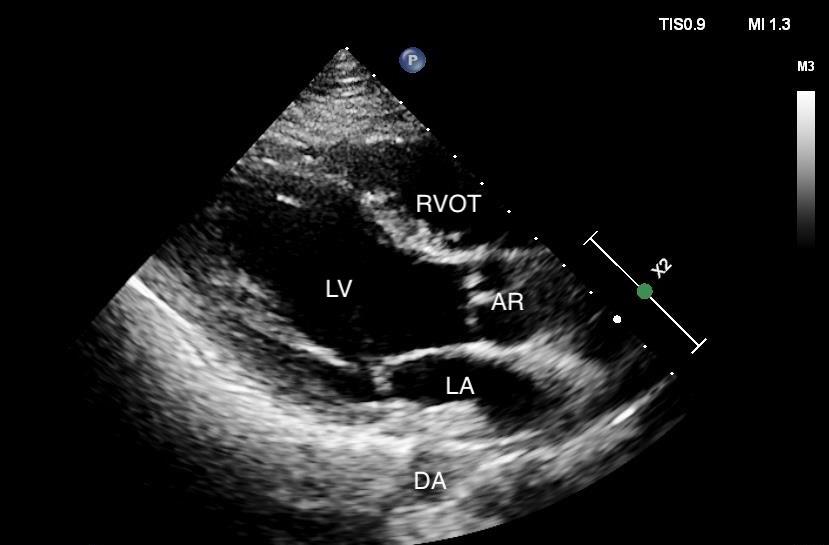

In the case covered in this article, an 85-year-old man with septic shock caused by a perforated sigmoid colon was profoundly hypovolemic and required crystalloid resuscitation and dual vasopressors. Ultrasound revealed that his internal jugular vessels were completely collapsible. Initial attempts to place the catheter were unsuccessful due to vessel collapse. The Trendelenburg position did not adequately dilate the internal jugular vein, as shown in Image 1. However, using a passive leg raise, significant dilation of the internal jugular vein was observed, enabling successful cannulation (Image 2).